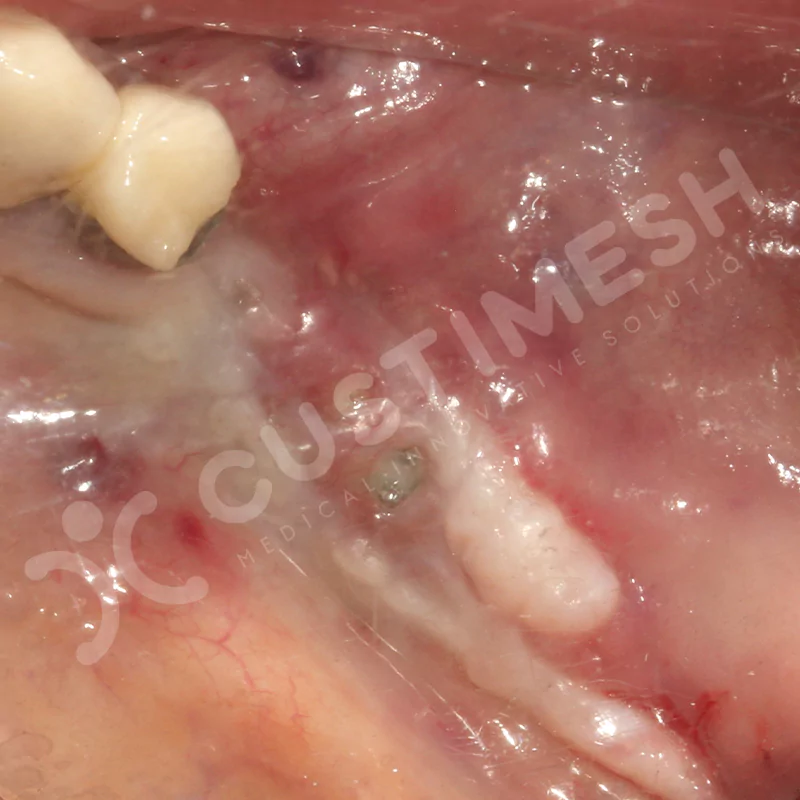

VAKA 2